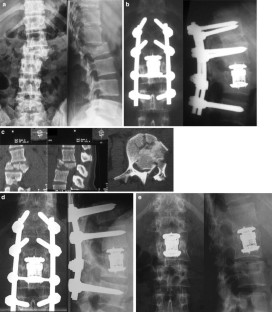

In the operative treatment of spinal injuries, the reconstruction of the anterior column of the thoracolumbar spine is still controversial. We conducted a prospective clinical study to investigate the clinical and radiological outcome of 50 patients treated with a vertebral body replacement of adjustable height (Synex™). Fifty consecutive patients were evaluated during in-patient treatment and at 12 and 20 months post-operatively in clinical notes and radiographs. 38/50 patients were operated for traumatic fractures. Out of 50 patients 45 attended the follow-up clinic 1 year post-operatively and 39 of these patients were examined after 20 months. Twenty-five patients returned to pre-injury activities within 1 year. This number increased to 29/39 patients at 20 months. Seventy-three percent of the patients returned to their job. After 1 year 25/45 patients complained of little or no back pain and 6 months later six patients were limited in their back function. At 1 year only three patients complained of surgical site pain which was improved at their final follow-up at 20 months. Individual satisfaction was determined using a score on a visual analog scale containing 19 questions on back pain, and functional limitation of the spine that has to be filled in by the patients at three different points of time. The score decreased from 87/100 pre-operatively to 65/100 at 1 year follow-up (P<0.001). The average permanent correction of the injured vertebra was 16.8° (88%) including 2.3° (12%) loss of correction at 12 months after operation. Bony integration was obtained in 83%. Early and intermediate outcome with the Synex™ vertebral replacement device for reconstruction of the anterior column appears promising. The loss of correction or reduction was only minimal. On the basis of our results we recommend the Synex™ implant as an alternative for the fixation and stabilisation of thoracolumbar fractures. However, long-term results and a clinically random control study are still required.